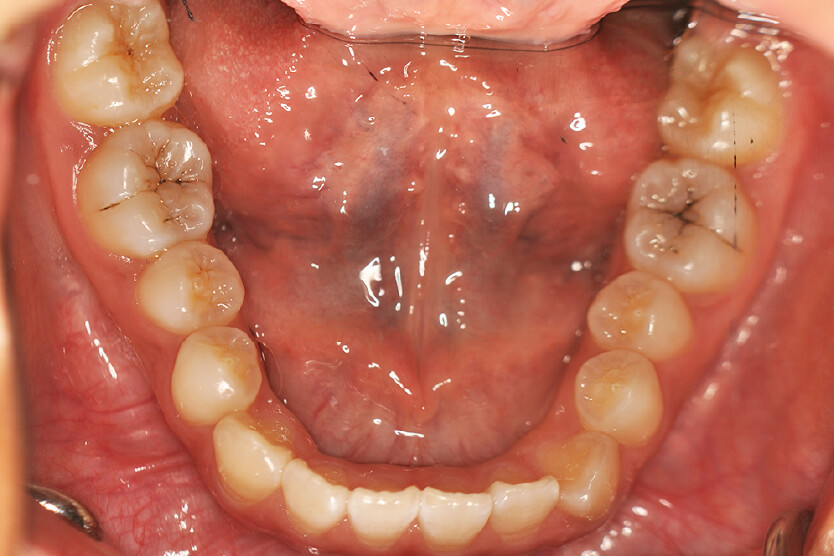

| 治療内容の詳細 | 初診時12歳の女性で、上顎前歯部の反対咬合を気にされ来院されました。 検査の結果、下顎前突、上顎前歯部叢生および上顎側切歯反対咬合を伴うアングルⅢ級不正咬合と診断しました。 治療としては、リンガルアーチを使用して、上顎側切歯を前方へ移動させ、反対咬合の改善を行い、マウスピース型矯正装置(インビザライン)で配列を行いました。 治療期間は1年5か月でした。 |